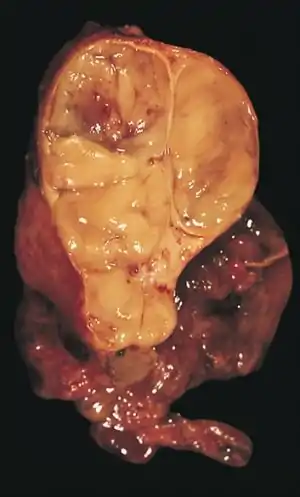

The diagnosis is made via histologic examination by a pathologist, after obtaining a tissue sample of the mass. Final tumor classification and staging is accomplished pathologically after formal surgical removal of the thymic tumor.

An encapsulated cystic thymoma.